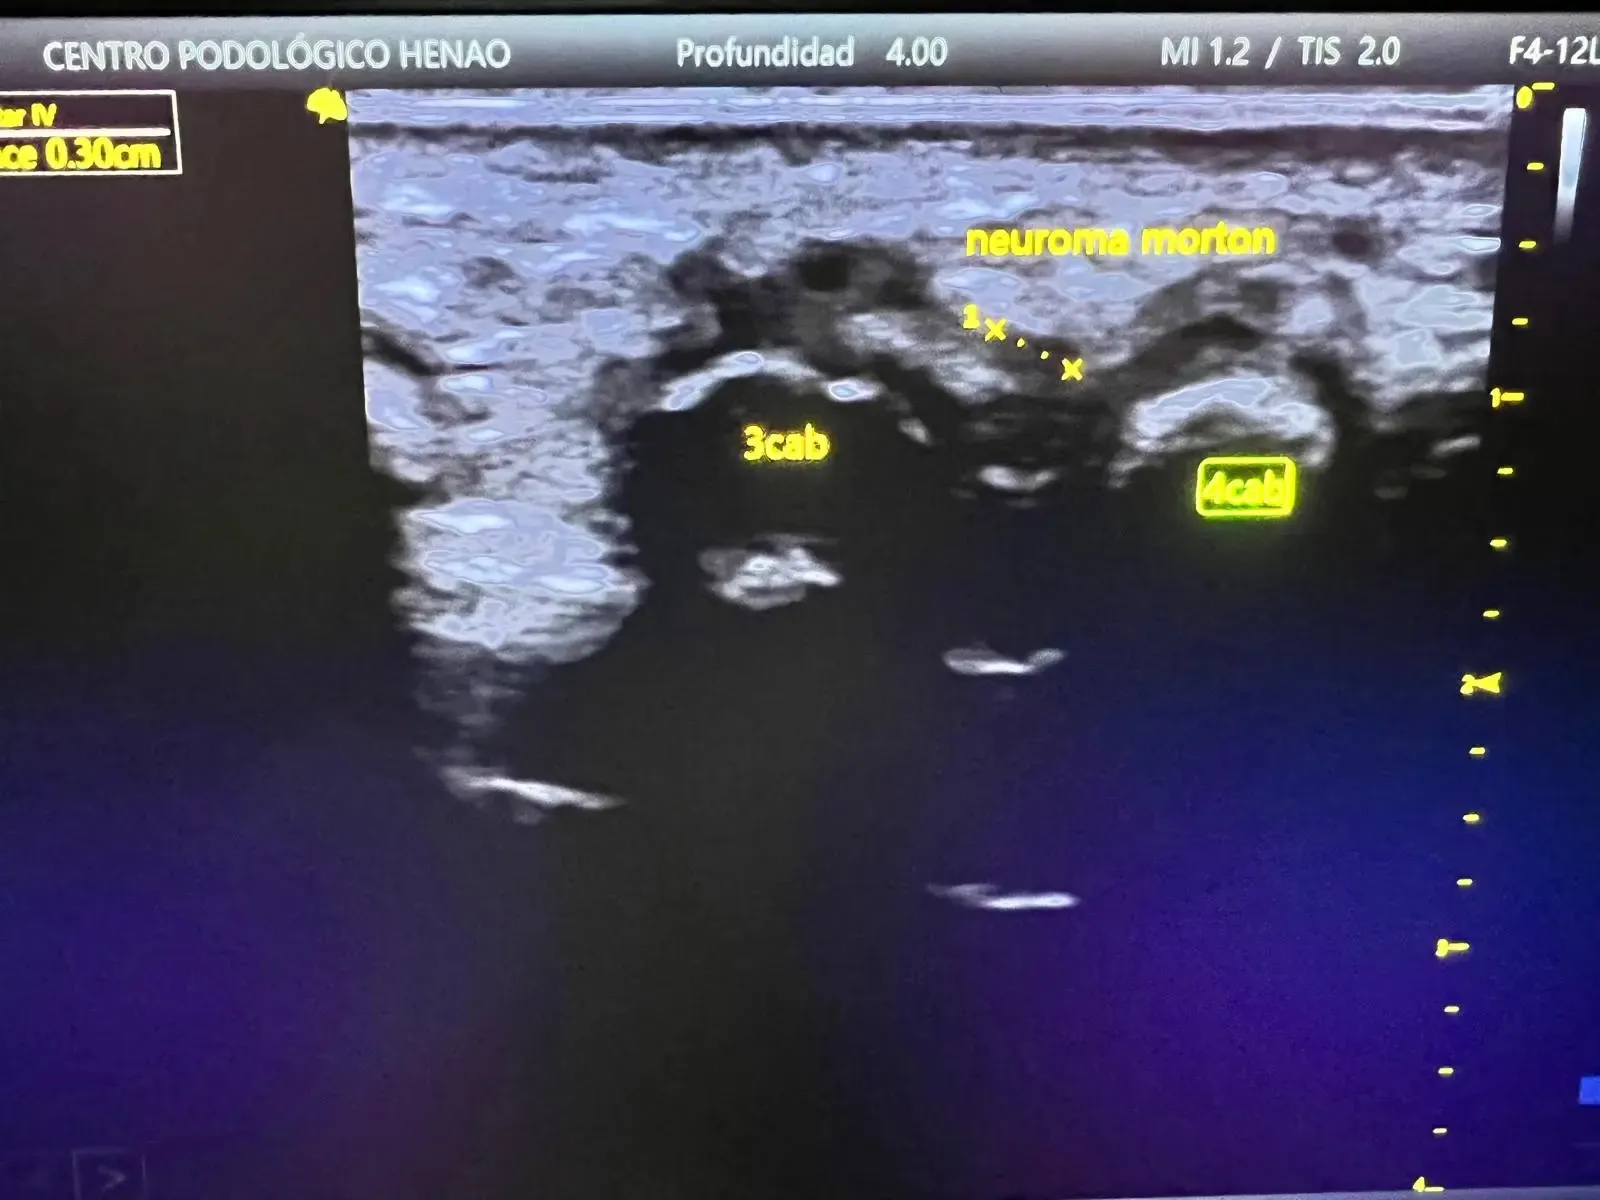

- Ecografía estática y dinámica: visualización directa del engrosamiento nervioso, medición de su diámetro y valoración de su comportamiento durante la compresión

La ecografía nos permite confirmar el diagnóstico de forma objetiva, clasificar el neuroma según su tamaño y establecer un plan de tratamiento basado en datos reales.